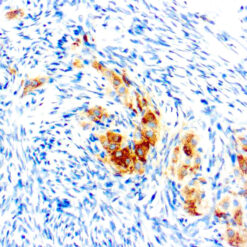

Synaptophysin (SYP02)

This antibody isspecific to a 38 kDa protein. Synaptophysin is an glycoprotein occurring in presynaptic vesicles of neurons in the brain, spinal cord, retina, vesicles of adrenal medulla and in neuromuscular junctions. This antibody reacts with neuroendocrine neoplasms of neural as well as epithelial types.

| Clone | SYP02 |

| Cellular Localization | Cytoplasmic |

| Positive Control Tissue | Pancreas |